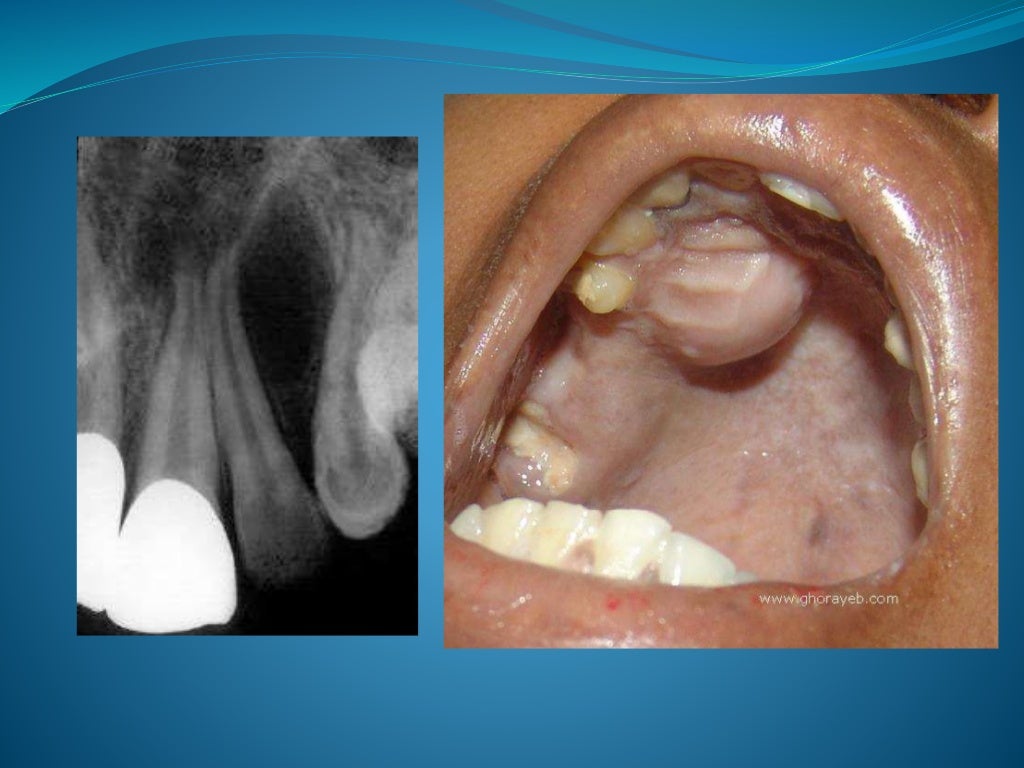

Cysts of the jaws What Causes Cysts In Jaw Bone jaw cysts and tumors are growths that can form from bone (including teeth) and soft tissue in your mouth. rarely, cancerous tumors form within your jawbone or from the tissue that’s involved in forming your teeth. what causes jaw tumors and cysts and who’s at risk? In most cases, the cause of the tumor or cyst isn’t. What Causes Cysts In Jaw Bone.

PPT Cysts of jaws PowerPoint Presentation ID5296491 What Causes Cysts In Jaw Bone what causes jaw tumors and cysts and who’s at risk? jaw cysts and tumors are growths that can form from bone (including teeth) and soft tissue in your mouth. rarely, cancerous tumors form within your jawbone or from the tissue that’s involved in forming your teeth. In most cases, the cause of the tumor or cyst isn’t. What Causes Cysts In Jaw Bone.

PPT CYSTIC LESIONS OF THE JAW PowerPoint Presentation, free download ID421716 What Causes Cysts In Jaw Bone rarely, cancerous tumors form within your jawbone or from the tissue that’s involved in forming your teeth. jaw cysts and tumors are growths that can form from bone (including teeth) and soft tissue in your mouth. In most cases, the cause of the tumor or cyst isn’t known. what causes jaw tumors and cysts and who’s at. What Causes Cysts In Jaw Bone.